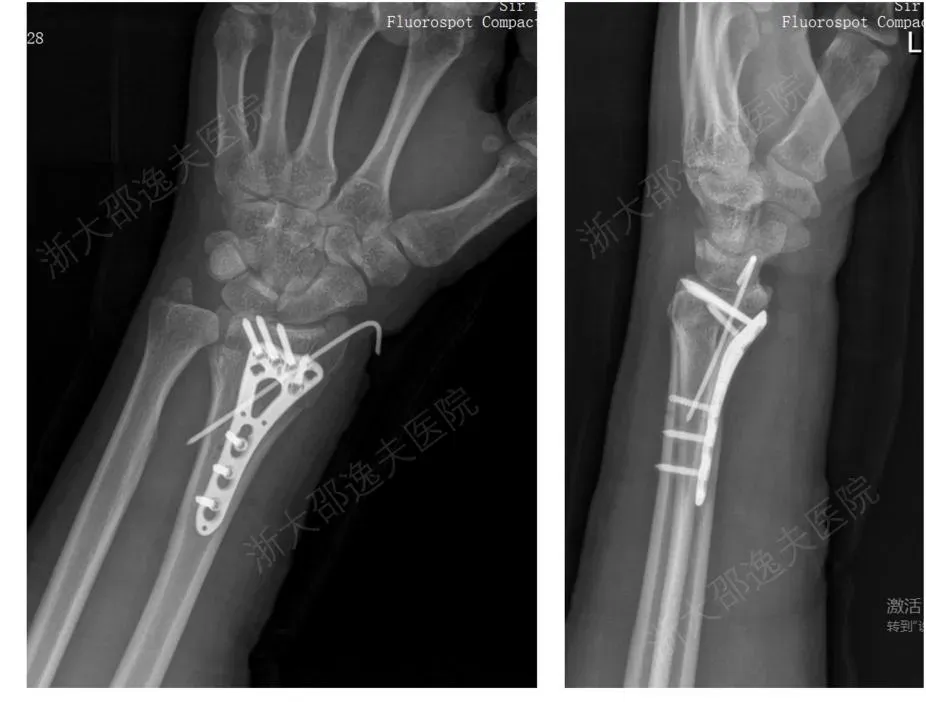

一位年轻工人因外伤导致腕部桡骨远端粉碎性骨折,传统治疗方案需大切口植入钢板螺钉,不仅创伤大、存在肌腱粘连或神经损伤风险,且需术后一年行二次手术取出。

桡骨远端骨折金属内固定治疗病例